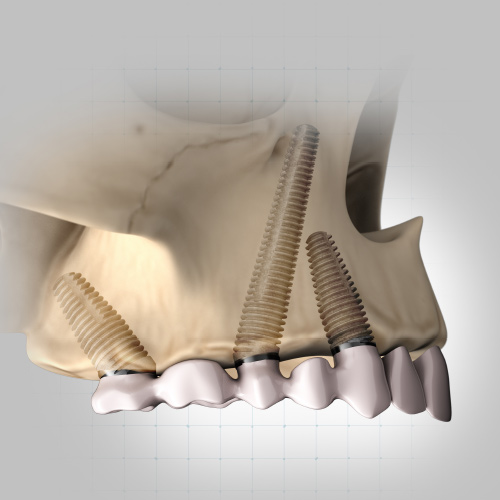

Dental Rehabilitation of the Atrophic Maxilla

Ankur Johri, DDS, MD, FACS

Friday, July 29, 2022

This Compendium eBook features a continuing education (CE) article presents important diagnostic and treatment planning principles of the All-on-4 treatment concept for the rehabilitation of the atrophic maxillary arch, and includes a case report illustrating free-hand implant placement using this treatment approach.